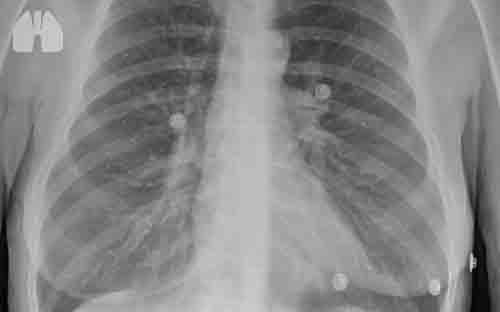

Namun, granuloma paru biasanya sulit terdeteksi tanpa tes pemindaian seperti rontgen dada atau CT Scan.